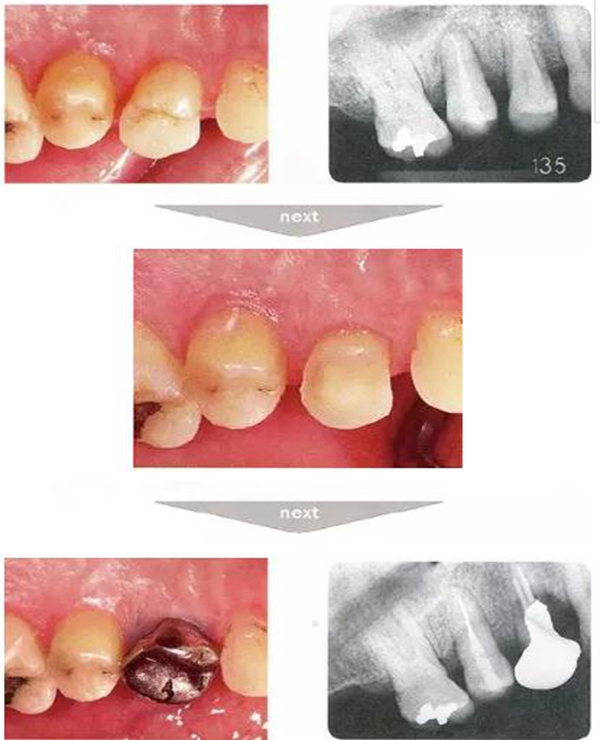

●與外傷相關(guān)的附著喪失①

右下4牙冠牙根破折案例。照片是破折前4個(gè)月拍攝的。牙周袋深度為3mm以下,牙周組織為正常狀態(tài)(右下5是以前由智齒矮小齒移植而來(lái))。破折后,舌側(cè)咬頭破折至傾斜的牙根處,破折片與牙齦相連。

去除破折片進(jìn)行了修復(fù)治療。3年后,上頜腭側(cè)有6mm、近中有4mm的牙周袋。X片可觀察到嚴(yán)重的骨吸收現(xiàn)象。可推斷出是破折引起的附著喪失。